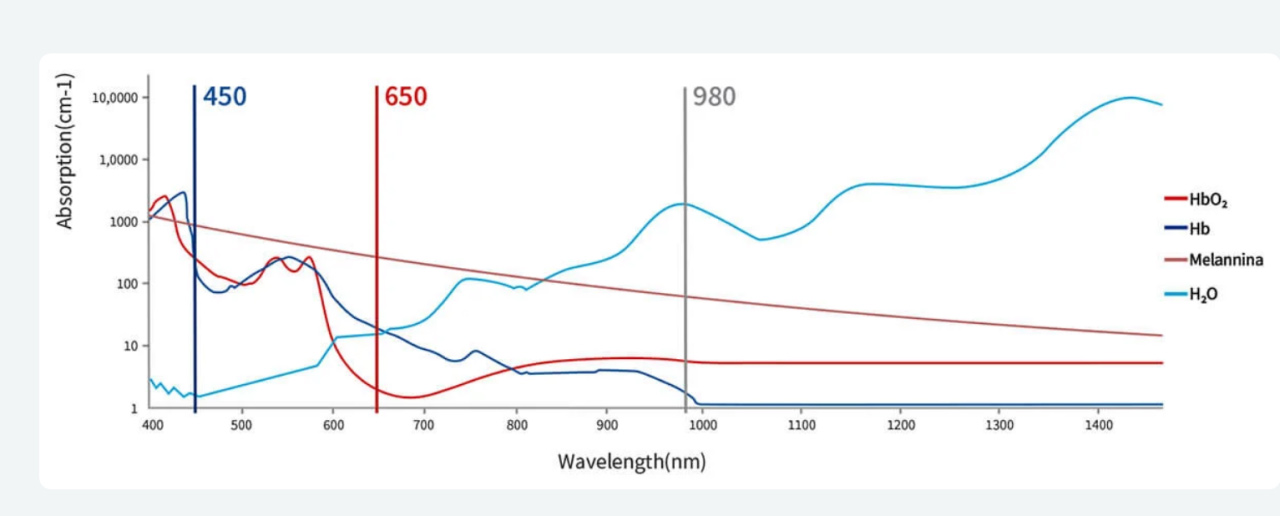

AZUL 450 nm

A 450 nm se alcanza el pico de máxima absorción de la hemoglobina, lo que permite un corte y una coagulación eficientes sin contacto a muy baja potencia, minimizando al mismo tiempo el daño térmico.

ROJO 650 nm

Terapia láser de baja intensidad (LLLT) / Fotobiomodulación para una cicatrización más rápida de las heridas y tratamientos dentales sin dolor.

IR 810/980 nm

Las longitudes de onda infrarrojas de 810/980 nm proporcionan una penetración profunda para una desinfección excepcional en tratamientos periodontales, endodóncicos y de implantes. Su excelente absorción por el agua mejora la ablación tisular, garantizando resultados de tratamiento eficaces y precisos.

Más allá de las ventajas individuales de 450 nm, 650 nm y 810/980 nm, el láser dental azul S3 amplía aún más su valor clínico mediante la emisión mixta de 980 nm + 650 nm. Esta emisión simultánea de doble longitud de onda combina la profunda penetración de 980 nm con los beneficios de la fotobiomodulación de 650 nm, lo que contribuye a la reparación de tejidos blandos, el alivio del dolor y el tratamiento antiinflamatorio en una gama más amplia de escenarios terapéuticos.